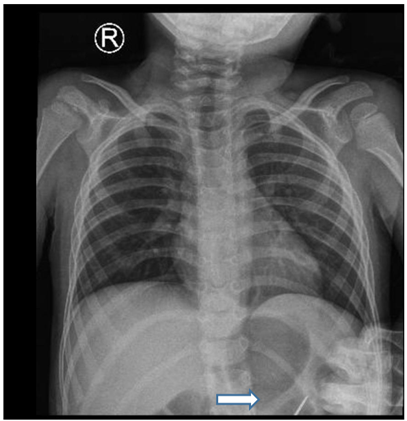

A follow-up chest X-ray, performed one day prior to the scheduled surgery, unexpectedly showed the FB in the stomach. As explained by the mother that the child had an episode of cough, six hours later, another X-ray revealed the FB in the distal small bowel. The patient's mother was instructed to observe his stools for passage of the FB. Two hours after the last X-ray, the FB was passed uneventfully with the stool.

Figure 3: X-ray showed foreign body in stomach.